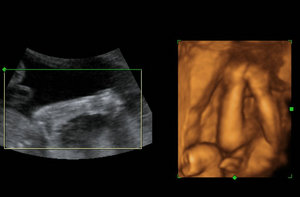

四维彩超哪里比较好?玛丽亚的专家对此表示到,随着经济的发展,越来越多的孕妈妈们开始重视孕期检查了,而在孕期检查中,最重要的一项就是进行胎儿畸形筛查,而四维彩超检查则是当前备受哈市产妇青睐的一项先进的排畸检查。

哈尔滨玛丽亚妇产医院专业为女性进行四维彩超的检查,可以提供科学、准确的检查结果,让孕妈妈们平稳度过怀孕期。而且我院自建院以来一直都很坚持“与世界先进医疗同步”的医疗理念,典雅时尚大气的候诊大厅区域,温馨私密性的独立诊室和舒适洁净的家庭式病房,以及具备符合国际标准的优质陪护服务,努力打造成为具有现代女性医学前沿和鲜明特色的专家型的医院。